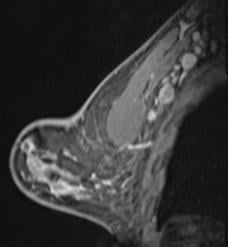

55-year-old woman who underwent screening mammogram and ultrasound 7 days after first COVID-19 vaccination dose. Screening mammogram and US demonstrated unilateral left axillary lymph node with cortical thickness of 5 mm on ultrasound (not shown). BI-RADS category 0 was assigned. Ultrasound from diagnostic work-up performed 7 days later showed no change in lymph node size. BI-RADS 3 was assigned.

Shabnam Mortazavi, M.D., of the University of California at Los Angeles reviewed electronic medical records to identify women with post-COVID-19 vaccination adenopathy found from December 2020 to February 2021. For mammography, Mortazavi considered a node abnormal when its size, shape, or density was deemed disproportionate to other axillary nodes (ipsilateral or contralateral). On ultrasound, she deemed a node abnormal based on subjective assessment for cortical abnormalities, including focal or diffuse thickening greater than 3 mm, as well as nodal prominence compared to the contralateral axilla (when available). For MRI, Mortazavi considered a node abnormal when asymmetric in size and/or number to the contralateral axilla.

Twenty-three women exhibited axillary adenopathy ipsilateral to the vaccinated arm on screening or diagnostic breast imaging, and according to Mortazavi, “13% were symptomatic (axillary lump with possible tenderness).” Meanwhile, the adenopathy was detected incidentally on screening breast imaging in 43% (mammography, 5; ultrasound, 2; both mammography and ultrasound, 1; high-risk screening MRI, 2) and on diagnostic imaging for other reasons in 43% (BI-RADS 3 follow-up for breast finding, 3; screening callback for other reason, 2; non-axillary breast pain or lump, 5). Noting that the median interval between the first vaccine dose and imaging showing the abnormal node was 9.5 days, Mortazavi’s results counted a total of 57% of women with one abnormal node. BI-RADS 2 was assigned in one woman, BI-RADS 3 in 21 (ultrasound in 4–24 weeks), and BI-RADS 4 in one.